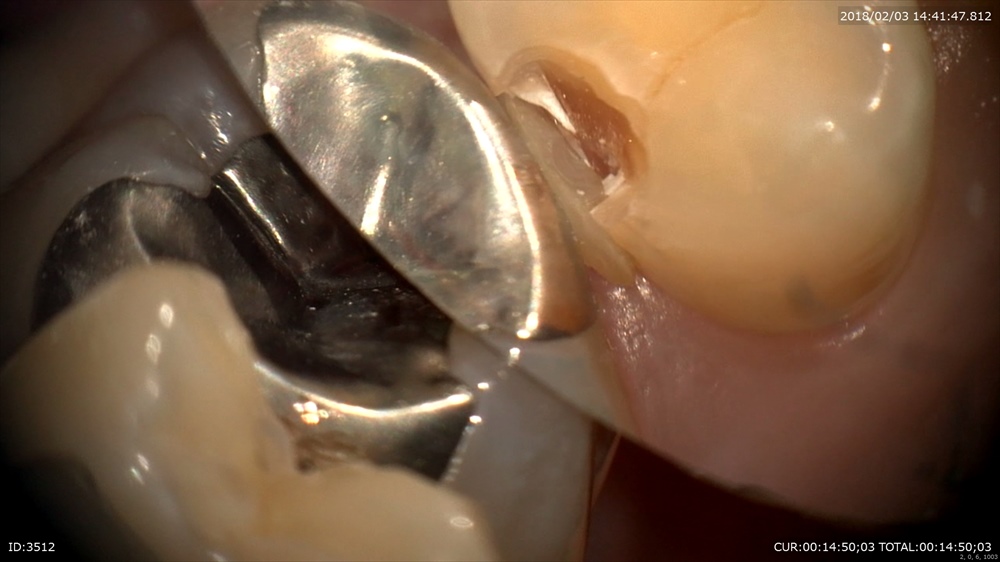

歯周病治療が終わり次のステップ。銀歯のブリッジが入っています。一見なにもない。症状もありません。歯科ドックでこの下に大きな虫歯が発見されました。本当でしょうか?のりが挟まっている。ということはここに隙間がある。=ここから細菌の進入が!!

わーーー

ほら。歯科ドック受けてよかったですね。

手前もぼろぼろ。でも救えます。まずは即席で仮歯を。ここが大切。むき出しになった歯は感染します。

次回から歯茎の調整にはいります。安心!!